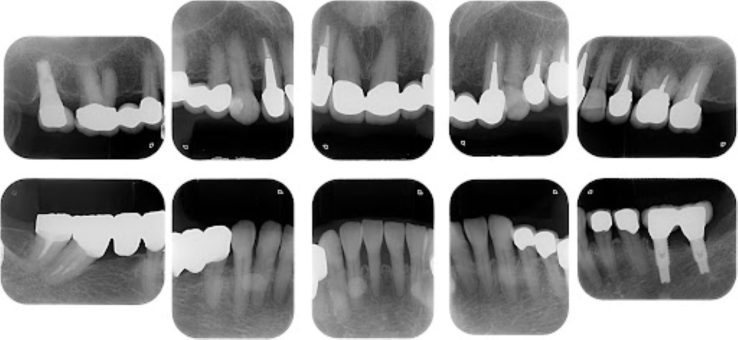

| 主訴 | 全顎治療希望、全顎的に歯が動く、奥の歯がなくて噛めない。できるだけ綺麗で噛めるようになりたい。 |

| 治療内容 | 全顎的に歯周病、前歯部の被蓋が深く、重度歯列不正が認められるため、 歯周外科を含む歯周治療、矯正治療、インプラント治療、セラミックによる補綴治療後メインテナンスに移行しました。 |

| 治療費 | 5,060,000円(税込)(インプラントすべて含む) |

| 治療期間 | 2年4ヶ月 |

| 治療回数 | 90回 |

| 想定されたリスク | 矯正治療の後戻り、歯周病の再発、食いしばり(パラファンクション)によるセラミックの破折、歯の破折のリスクがありました。 |